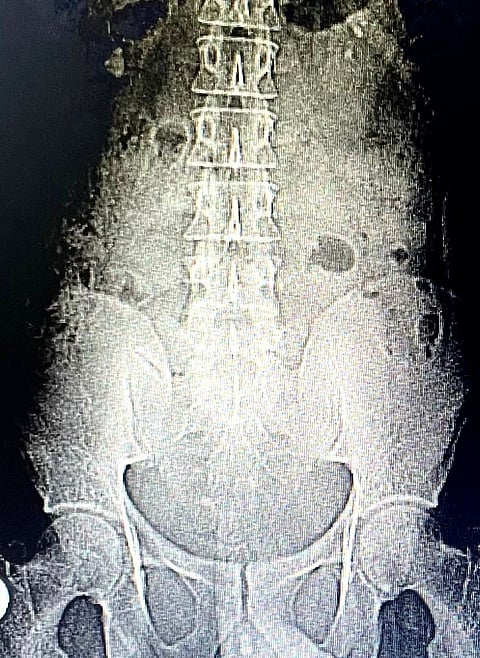

قالت "صحة الطائف"، اليوم الأحد: إن مريضًا وصل لمجمع الملك فيصل الطبي بالطائف في العِقد الثاني من العمر يشكو آلامًا شديدة بالبطن، وبالكشف تبيّن وجود حصوات في المثانة البولية والحالب والكلى.

وأضافت في تصريحٍ لـ"سبق": أنه على الفور تقرر إجراء منظار لتفتيت هذه الحصوات واستخراجها؛ حيث تم وضع المريض مستلقيًا على ظهره للسماح بعمل منظار المثانة البولية والحالب.

وتابعت: في الوقت نفسه جرى عمل منظار الكلى لاستخراج حصوات الكلى.

وأكدت أن منظار الكلى في وضع المريض مستلقيًا على ظهره يعتبر تحديًا؛ نظرًا لأنه عكس الوضع المعتاد، حيث يكون المريض مستلقيًا على البطن، ويحتاج لمهارة خاصة.

ولفتت إلى أن المنظار استغرقَ قرابة الساعتين؛ لتفتيت واستخراج كل الحصوات بالمثانة البولية والحالب والكلى بمساعدة جهاز الليزر.